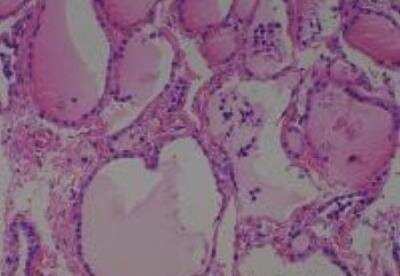

Hematoxylin & Eosin Stain: Human Common Tissue MicroArray (Normal Adjacent) [NBP2-30215] - 103. Stomach